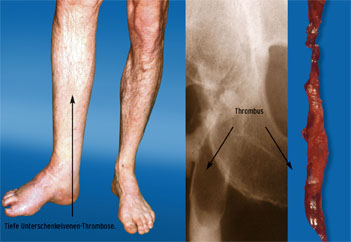

Thromboseneigung („thrombotische Diathesen“)

Im Hinblick auf Ursachen, Entstehungsmechanismus, Beschwerdebild, Art der Behandlung und Wahl der geeigneten Prophylaxe unterscheiden wir Thrombosen in der arteriellen und in der venösen Strombahn. Im schnell fließenden arteriellen System sind es vor allem arteriosklerotische Gefäßwandschädigungen, die eine Aktivierung der Thrombozyten auslösen und so zu einer Thrombusbildung in Herzkranzgefäßen (Myokard-Infarkt), hirnversorgenden Arterien (Schlaganfall), Äderchen am Augenhintergrund (Retinagefäßverschluss) oder Bein- und Beckenarterien (arterielle Verschlusserkrankung) führen. Im langsam fließenden venösen Stromgebiet ist demgegenüber Stillstand des Blutflusses („Stase“) in Verbindung mit einer abnorm gesteigerten Gerinnbarkeit („Hyperkoagulabilität“) Ursache von Thrombosen der tiefen Bein- und Beckenvenen. Die Entstehung von Venenthrombosen wird durch Ruhigstellung von Gliedmaßen (z.B. Gipsverband nach Knochenbruch) gefördert.